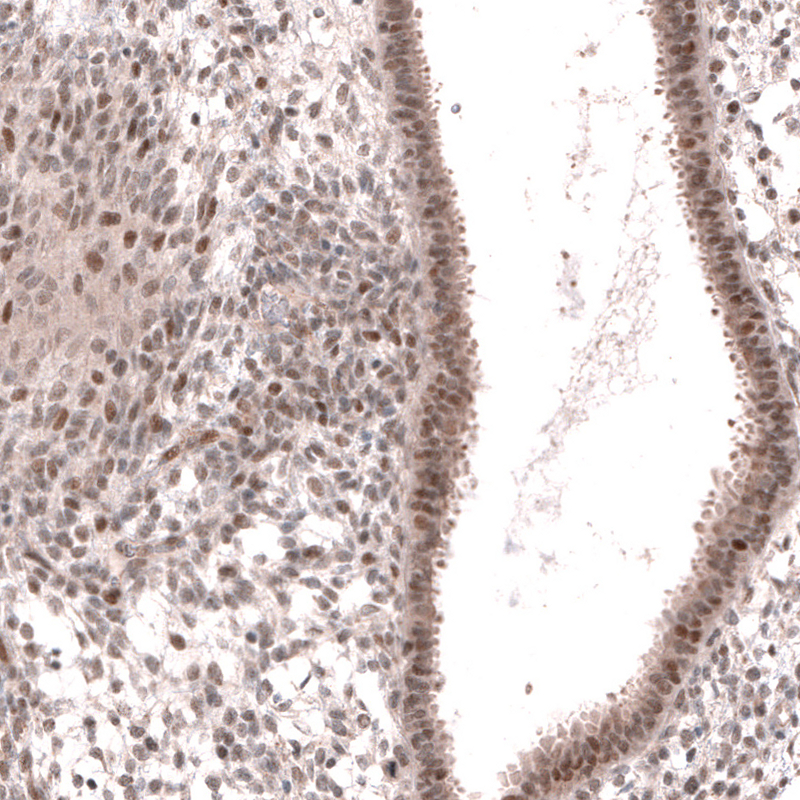

Immunohistochemical staining of human endometrium shows moderate nuclear positivity in glandular and stromal cells.